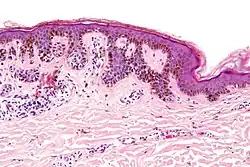

| Intradermal nevus | Within the dermis. | A classic mole or birthmark. It typically appears as an elevated, dome-shaped bump on the surface of the skin.[3][4] |

|

-

Small dermal nevus, with nests of nevus cells (arrows)